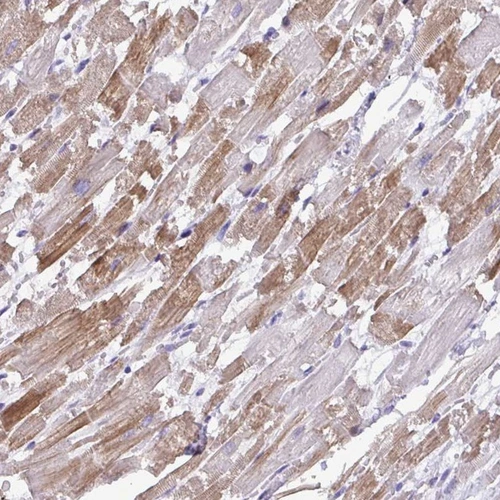

Immunohistochemical staining of human heart muscle shows cytoplsmic positivity in myocytes.